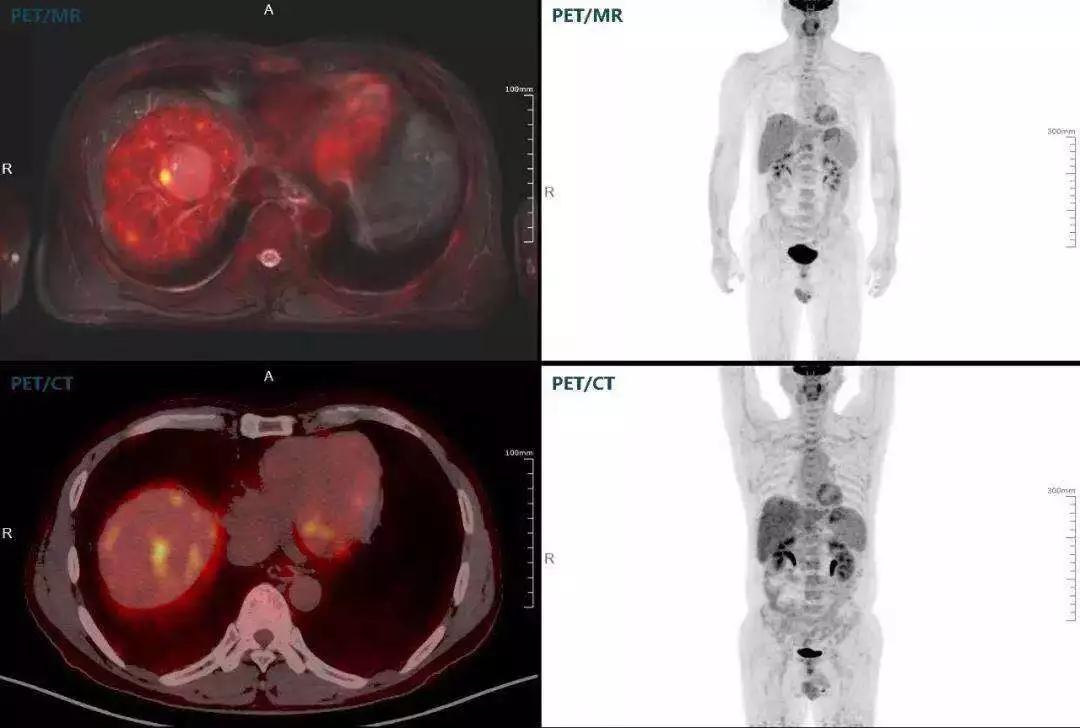

聯(lián)影“時(shí)空一體”超清TOF PET/MR搭載的壓縮感知技術(shù),能夠同時(shí)實(shí)現(xiàn)16期成像,精準(zhǔn)捕獲肝臟動(dòng)態(tài)影像的每一瞬間,同時(shí)兼顧早期與晚期等全部期相的完整病灶信息,實(shí)時(shí)、全方位鎖定病灶。同時(shí),基于其2.8mm超高分辨率,能夠精細(xì)呈現(xiàn)腫瘤邊界信息,捕捉局部微小病灶與遠(yuǎn)端轉(zhuǎn)移灶,助力醫(yī)生精準(zhǔn)診斷。

(對(duì)于同一例肝臟惡性腫瘤,PET-CT與PET/MR成像對(duì)比??梢钥吹?,聯(lián)影PET/MR圖像對(duì)腫瘤邊界和FDG高濃聚區(qū)域清晰顯示。)